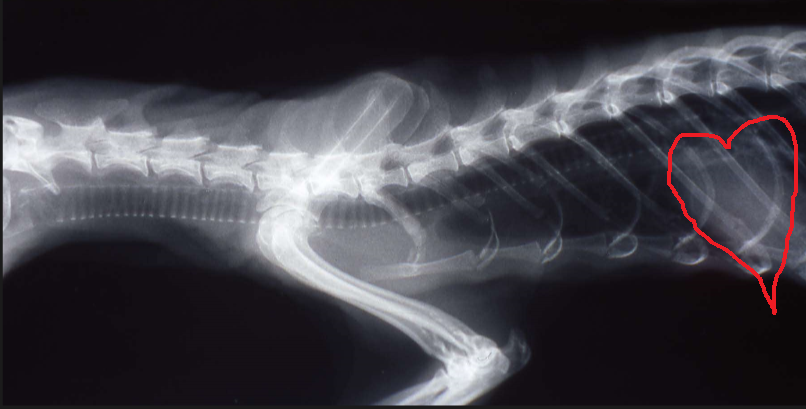

What is this doctor listening to on this ferret?

The heart.

It sits more caudally than the typical elbow landmark.